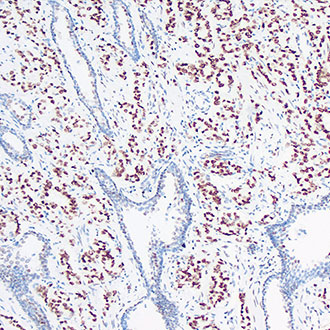

PMS2

PMS2 -